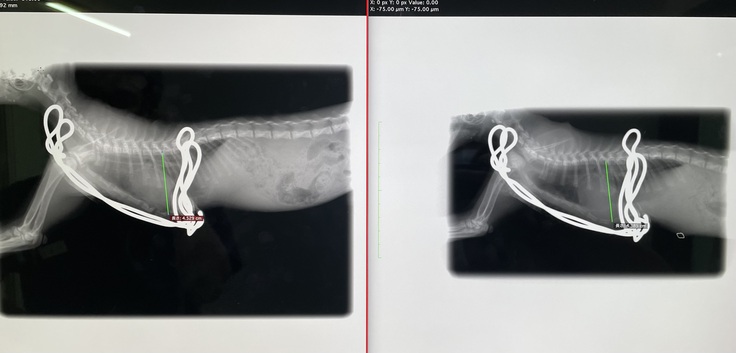

【本日撮影のレントゲン写真】

(左)本日 (右)7/9手術直後撮影

術後はじめてのレントゲンを撮りました。

骨も戻ることなく、経過は順調です。